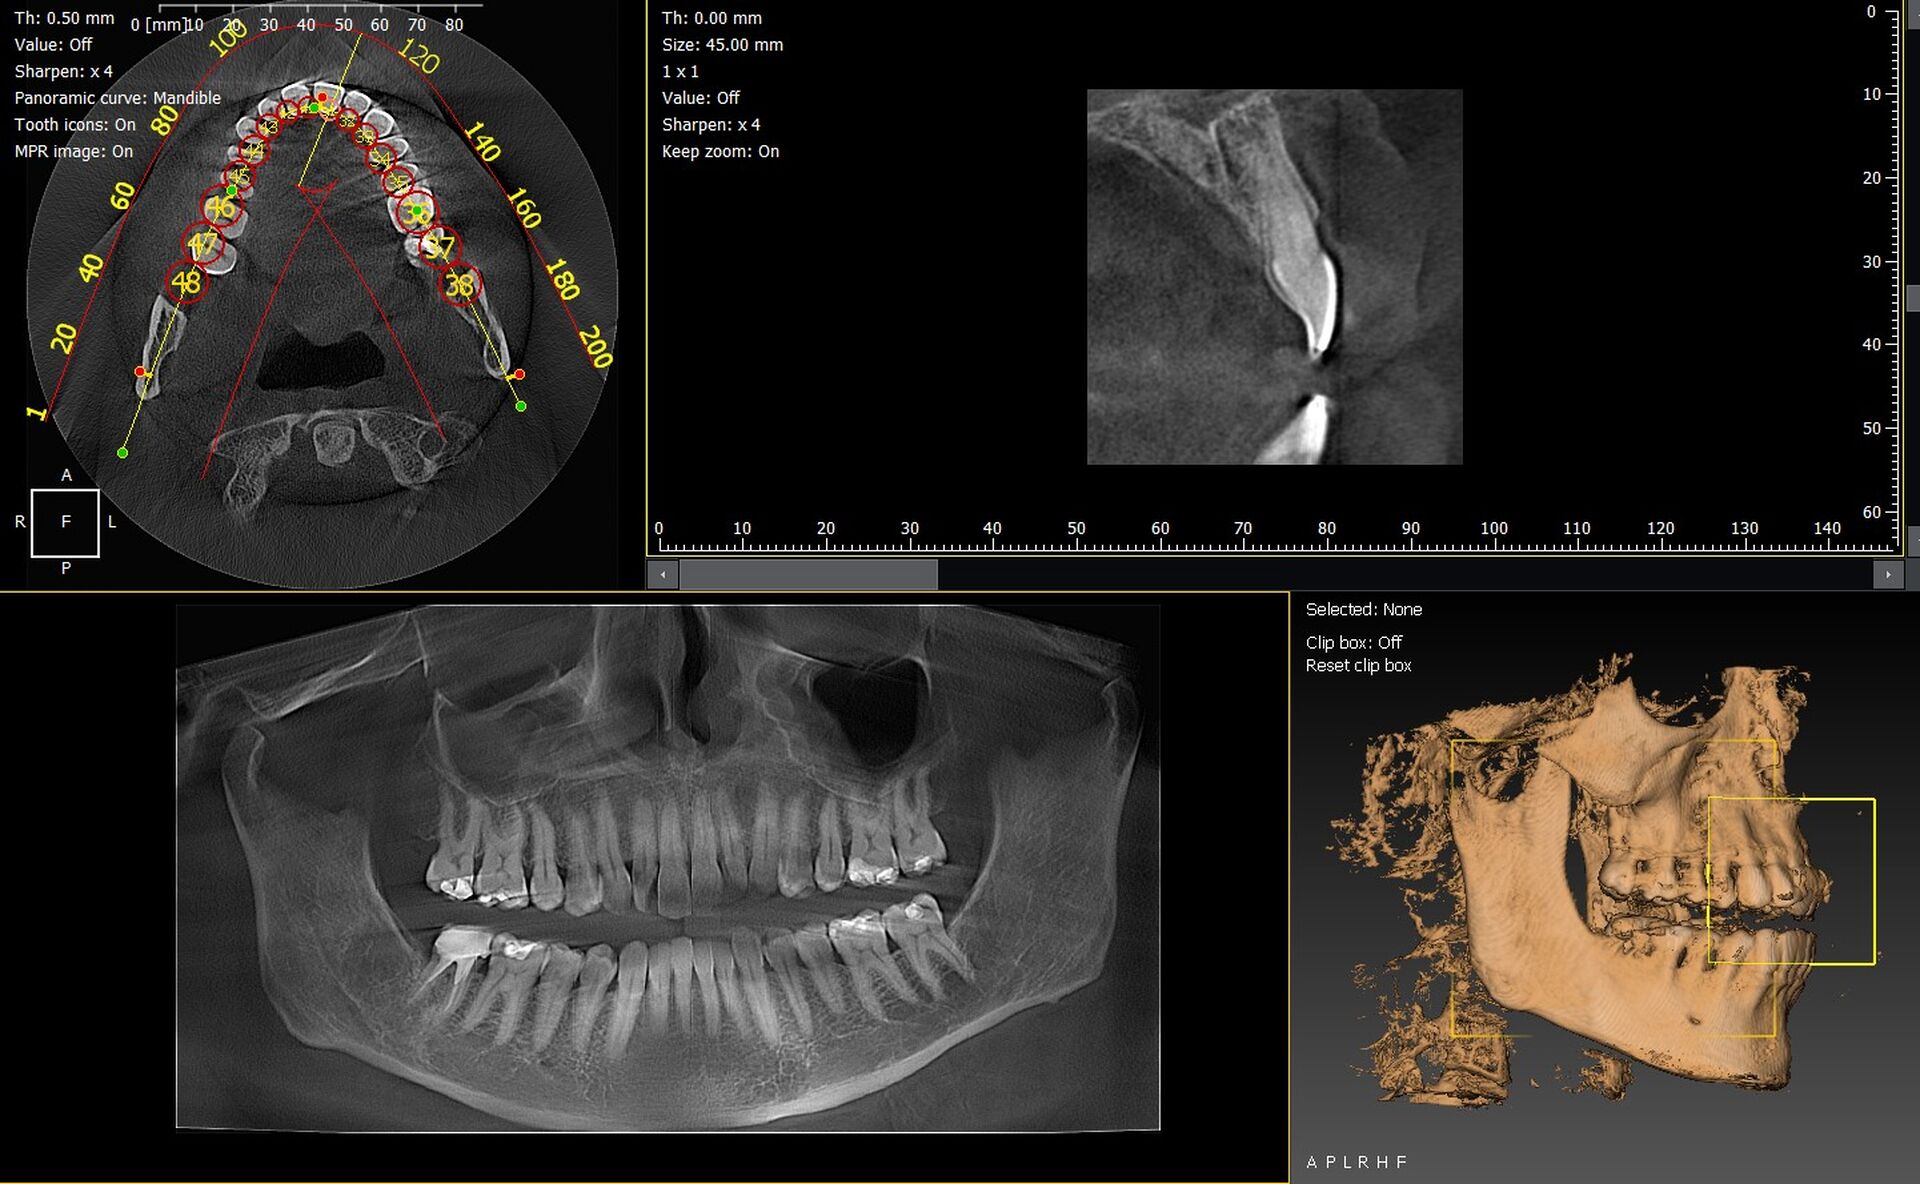

Les cabinets dentaires de Manosque et des Alpes de Haute Provence 04 adoptent de plus en plus l’imagerie 3D afin d’améliorer la précision de leurs diagnostics. Les systèmes panoramiques CBCT constituent aujourd’hui un outil indispensable pour l’implantologie, la chirurgie orale, l’endodontie et l’orthodontie. Parmi les solutions les plus performantes, les modèles Dürr Dental VistaVox et Owandy I-Max 3D offrent un rendu d’image de haute qualité, une ergonomie optimisée et une parfaite intégration dans les cabinets dentaires de Manosque.

Dürr Dental VistaVox : une précision d’imagerie adaptée aux diagnostics exigeants

Le VistaVox propose un volume 3D optimisé pour l’analyse de l’arcade complète, permettant une lecture fine des structures complexes : canal mandibulaire, sinus maxillaires, racines, zones péri-apicales et anatomies délicates.